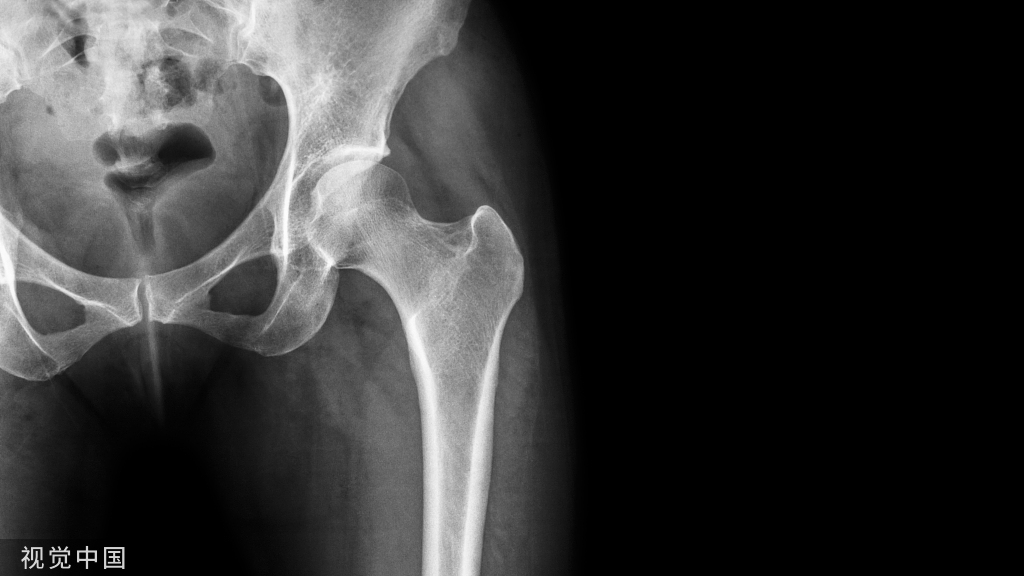

X线检查,确认骨折愈合

内固定物的识别,厂家,型号,接口,相应的器械